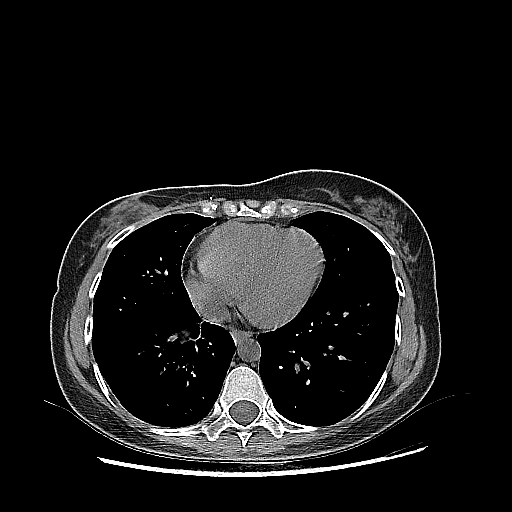

Image Grid

4Γ—3 grid: Rows show different image types (Original NATIVE, Reconstructed NATIVE, Original VENOUS, Generated VENOUS), Columns show windowing techniques (No Window, Lung Window, Mediastinum Window)

Reconstructed NATIVE CT scan (cycle consistency)

Full window (WL 1023.5, WW 4095 β†’ Low βˆ’1024, High +3071)

Generated VENOUS CT scan (A→B translation)